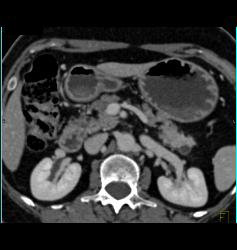

Diagnosis

Intraductal Papillary Mucinous Neoplasm (IPMN) With Normal Splenic Artery and Vein